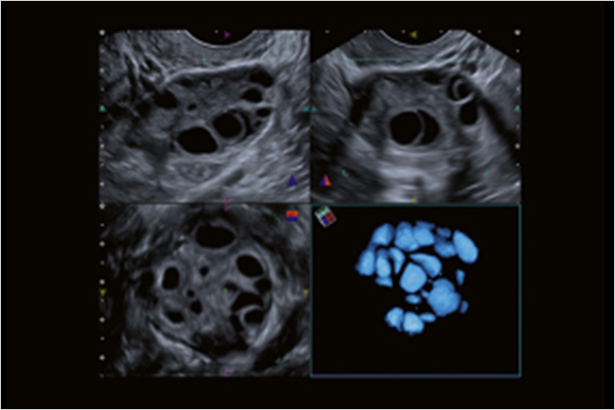

從容積圖像中自動識別有特征的封閉空間,并進行體積的測量,測量結果接近真實情況。

當使用寬帶iDMS探頭時,你可以調整圖像采集的聲束厚度。在對微細血流成像時,可以完整采集沿聲束方向立體擴散的血管結構。